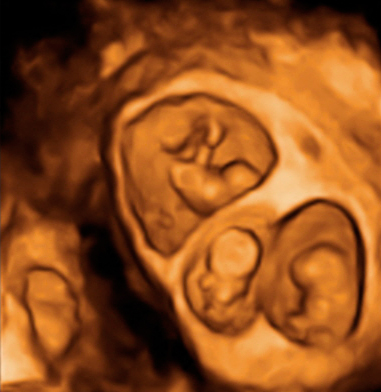

Ecografía 4D de la semana 12: Gemelos contrapeados

Ecografía en 4D de gemelos de 12 semanas "contrapeados" En este caso, el gemelo que "baila" es el que está en parte inferior de la imagen o cabeza abajo.